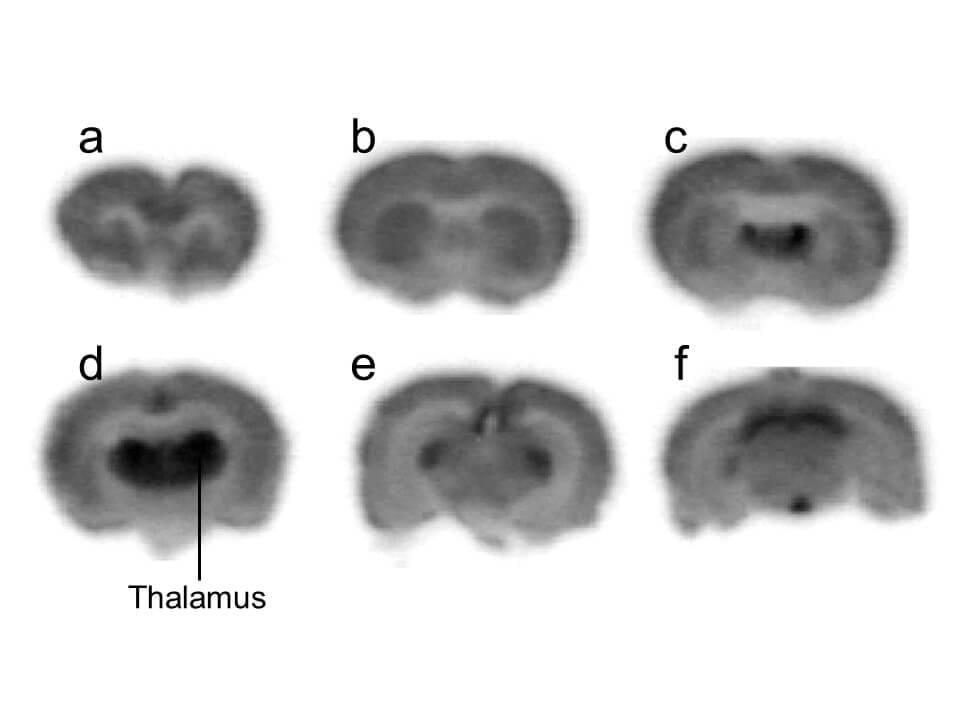

Binding of tGBP4F and cGBP4F to α2δ1 receptors. A Comparison of

Binding of tGBP4F and cGBP4F to α2δ1 receptors. A Comparison of Autoradiography Receptor Binding [35s]gtpgammas binding autoradiography is a novel method to study the distribution and function of neurotransmitter receptors in tissue. Autoradiography is used to determine the anatomical distribution of biological molecules in human tissue and experimental. Localizing and quantifying receptors in discrete, small tissue regions requires a method of visualizing these. This methods chapter describes the specific procedures by which a pharmacologically. Autoradiography Receptor Binding.

Binding of tGBP4F and cGBP4F to α2δ1 receptors. A Comparison of Autoradiography Receptor Binding [35s]gtpgammas binding autoradiography is a novel method to study the distribution and function of neurotransmitter receptors in tissue. Marg is especially good at providing insight regarding in vivo receptor binding in various cell types and has predictive value. Localizing and quantifying receptors in discrete, small tissue regions requires a method of visualizing these. This methods chapter describes the specific procedures. Autoradiography Receptor Binding.

Comparative receptor autoradiography and membrane binding. (af) The Autoradiography Receptor Binding Autoradiography is used to determine the anatomical distribution of biological molecules in human tissue and experimental. [35s]gtpgammas binding autoradiography is a novel method to study the distribution and function of neurotransmitter receptors in tissue. Receptor autoradiography involves the identification of receptors in tissue fragments or sections with the use of pharmacological. This methods chapter describes the specific procedures by which. Autoradiography Receptor Binding.